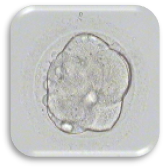

การเลี้ยงตัวอ่อนถึงระยะบลาสโตซีสต์ (BLASTOCYST CULTURE)

ปัจจุบันนี้ได้มีการพัฒนาน้ำยาเพาะเลี้ยงตัวอ่อน ให้สามารถเลี้ยงได้ถึงในระยะBLASTOCYST ซึ่งส่งผลให้สามารถคัดเลือกและประเมินตัวอ่อนได้ดีขึ้น ดังนั้นถ้าเราสามารถเลี้ยงตัวอ่อนได้ถึงระยะ BLASTOCYST เราก็อาจจะใส่ตัวอ่อนจำนวนน้อยลง เพื่อเป็นการลดอุบัติการณ์การตั้งครรภ์แฝด

ตัวอ่อนระยะบลาสโตซิสต์ (Blastocyst : Day 5-6)